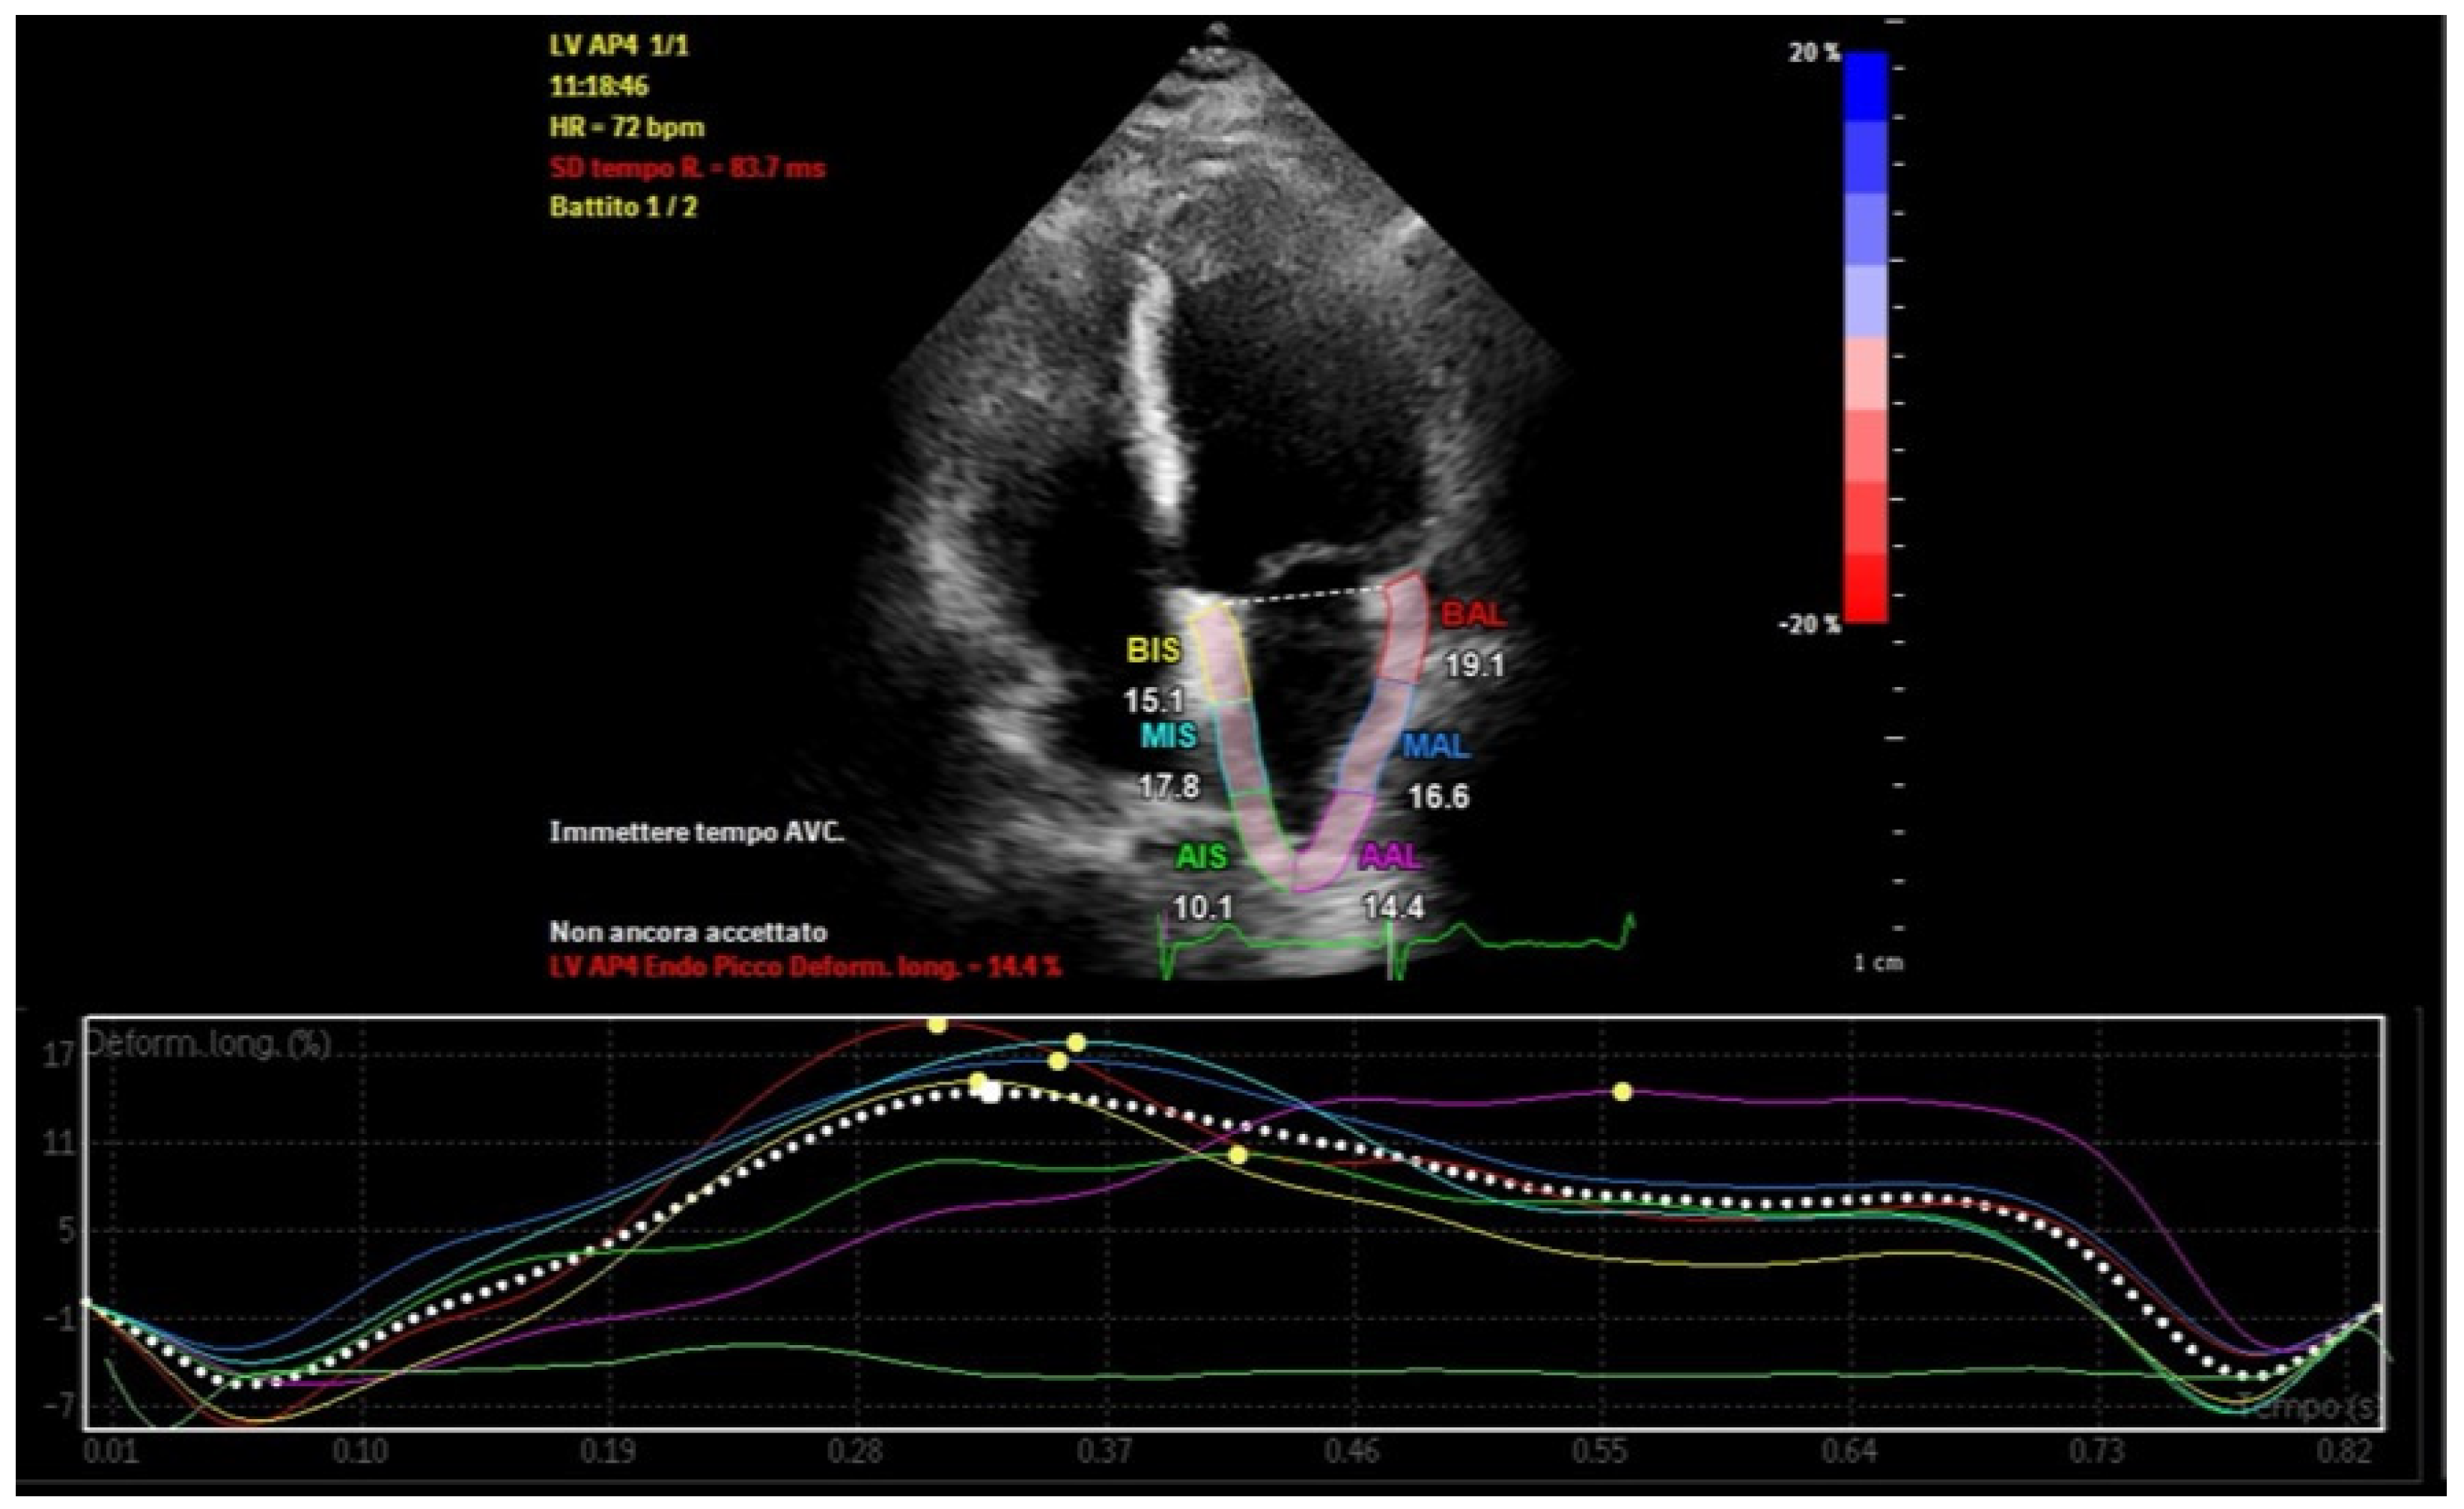

Atrial strain, assessed via speckle-tracking echocardiography, quantifies myocardial deformation and provides insights into atrial reservoir and contractile functions [23]. This technique allows early detection of subtle atrial dysfunction, even before structural abnormalities manifest [24]. Strain imaging also identifies and quantifies atrial dyssynchrony, which reflects temporal discrepancies in atrial deformation during the cardiac cycle (Figure 3) [25,26].

Figure 3.

Left atrial strain showing dyssynchrony in a patient with recurrent episodes of paroxysmal atrial fibrillation and abundant left atrial epicardial adipose tissue.

Regional dyssynchrony in strain patterns is a prominent feature in these patients, characterized by variability in time to peak strain (TTP) across atrial segments (Figure 6). This variability indicates asynchronous contraction, with the posterior and inferior walls of the left atrium—regions adjacent to EAT deposits—frequently showing the most delayed TTP. Strain curves in these segments often exhibit nonuniformity, with delayed or flattened peaks compared to unaffected regions. Segments nearest to large EAT deposits demonstrate the greatest dyssynchrony, underscoring the localized impact of EAT on atrial mechanics [55].

Figure 6.

Left atrial strain in a patient with abundant left atrial epicardial adipose tissue. Time−to−peak variability and reduced peak atrial longitudinal strain are recorded.

The global dyssynchrony index, defined as the difference between maximum and minimum TTP across all atrial segments, quantifies this dyssynchrony. In patients with increased EAT, the index is significantly elevated, often exceeding 20%, compared to less than 10% in healthy individuals [56,57]. This disparity highlights EAT’s role in disrupting atrial synchrony.

Global atrial strain, particularly PALS, is notably reduced in patients with increased EAT [58]. This reduction reflects impaired atrial deformation and further compromises mechanical function.